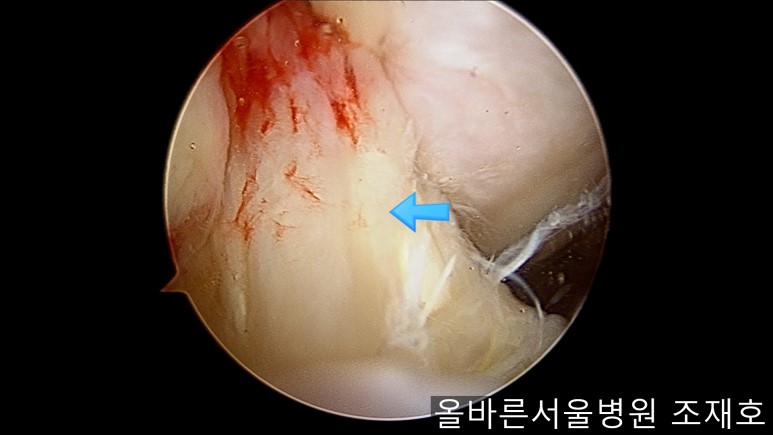

通过关节镜图像可看到:由于内侧股骨髁软骨损伤骨头已经显露出来。

胫骨上端的软骨损伤严重,也露出了骨头。

正是缺失软骨的部位碰到一起,引发剧烈疼痛,腿部逐渐变形。